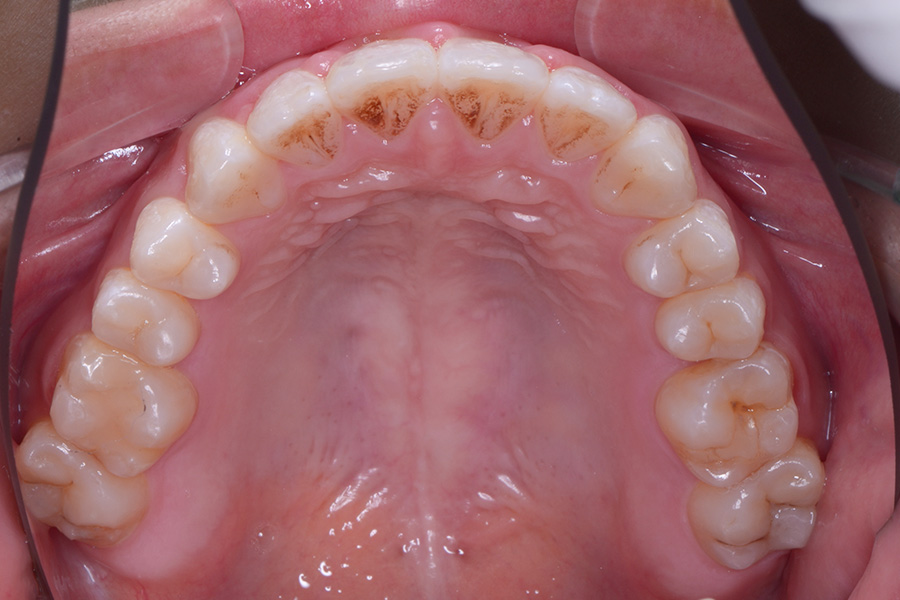

• 治療前